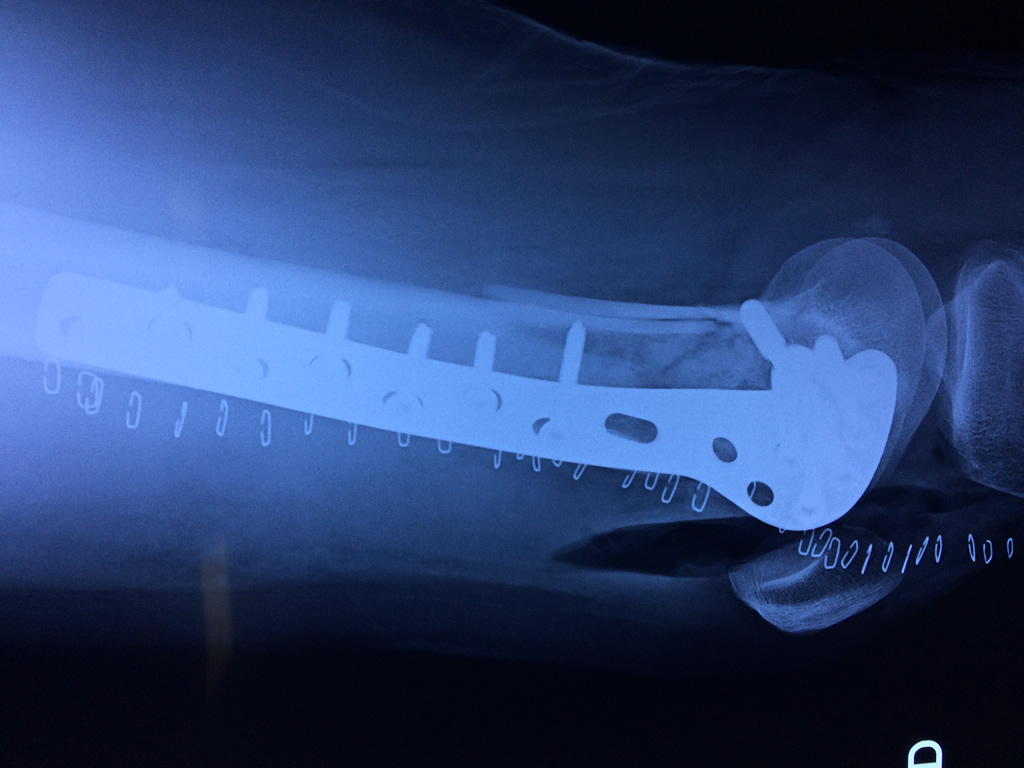

Cirugias en El Salvador - Fémur

El fémur es el hueso del muslo, el segundo segmento del miembro inferior. Es el hueso más largo, fuerte y voluminoso del cuerpo humano.